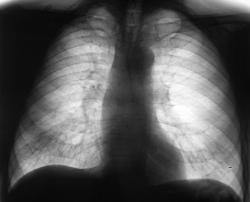

При расшифровки цифровых флюорограмм пациент "взят на контроль". Смутила правая верхушка и верхняя доля правого лёгкого.

ИзображениеИзображение

Произведено дообследование.